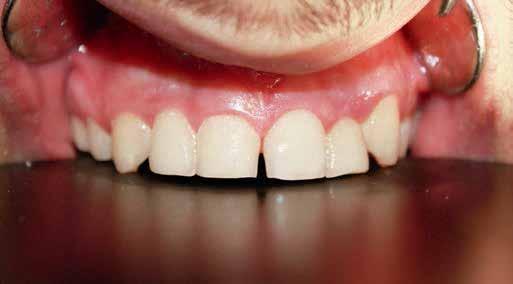

Material and method: immediate implant placement to replace non restorable teeth in the maxillary anterior region. Extraction was done and immediately an implant was inserted. Customized healing abutments were fabricated using Cervico mold and connected to the dental implant. After 3 months, intraoral scanning was done to fabricate a definitive crown.

Conclusion: Easy clinical technique to create proper emergence profile through customized healing abutment using the Cervico device. The use of Cervico device for the construction of customized healing abutments prepares soft tissue for the prosthetic stage preserving its contours and eliminating the need for reopening surgery for immediate as well as for early implant placement.

The prosthetic procedures for definitive restorations were performed 3 months after implant placement. The healing abutment was removed (Fig 10) scan body was placed in position and a digital implant-level impression was made using an intraoral scanner (Medit I 700 3D scanners) (16) (Fig 11,12)

Exocad was used to design the restoration (fig. 13) and was milled from a super translucent multilayered zirconia (KATANA Zirconia STML; Kuraray Noritake). The milled restoration was cemented on the Ti-base with a resin cement (RelyX Unicem; 3M ESPE). Then, the definitive restoration was connected to the implant, and the Ti-base screw was tightened to 20 Ncm according to the manufacturer’s instructions. The screw access channel was sealed with sterilized PTFE and photopolymerized composite resin (Filtek Supreme Ultra; 3M ESPE). The definitive restoration was evaluated for centric and eccentric occlusal contacts and then finished and polished (fig 14,15).